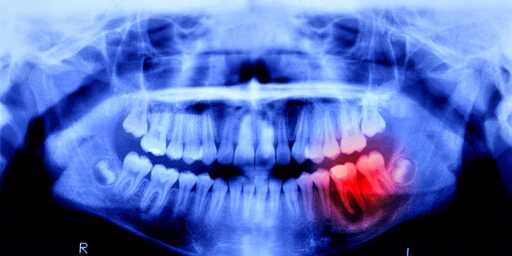

Now, scientists will see just how similar, because humans are undergoing a similar trial. Lasting 11 months, this study focuses on 30 males between the ages of 30 and 64—each missing at least one tooth. The drug will be administered intravenously to prove its effectiveness and safety, and luckily, no side effects have been reported in previous animal studies.

Gum disease could lead to tooth loss but the primary way people lose them is through infections due to cavities. The infection weakens the tooth and the jawbone it’s rooted in as well as can lead to loss of the root nerve. At a certain point the tooth is too loose or weak and has to be removed to prevent further infection and/or to treat the existing infection.